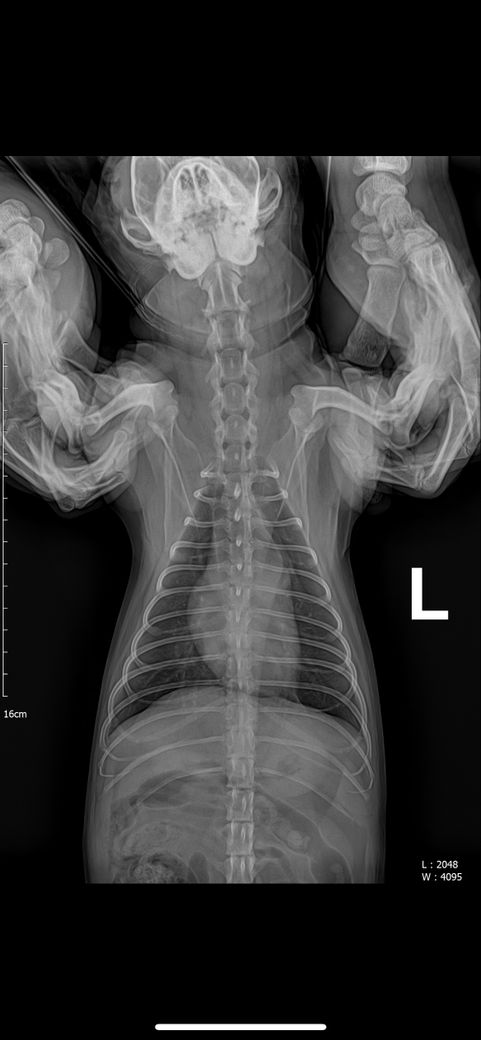

강아지 엑스레이에 문제점 있는지 봐주세요

강아지 엑스레이 문제 되는 곳 있는지 봐주세요 심장 크기랑 간이나 등등 문제 되는 곳이 있는지 궁금합니다 병원에선 문제 되는 곳 없다고 하시긴 했는데 조금 더 확실하게 알고 싶어서요

안녕하세요. 박창민 수의사입니다. 크게 문제되는 부분은 없는 거 같습니다. 또한, 엑스레이로는 정말 제한적인 정보만 얻을 수 있습니다. 더 많은 정보를 원하시면, 초음파 검사를 받으셔야 합니다. 감사합니다.

주치의의 판단이 옳은것으로 보입니다. 다만 좌측 슬개골의 내측 변위 양상 즉, 슬개골 탈구 상태가 있으니 이 부분에 대해 상담받으시고 수술 결정하시기 바랍니다.